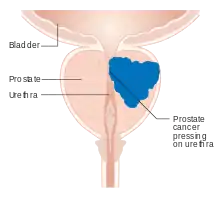

| |

| Position of the prostate | |

Pathophysiology

The prostate is part of the male reproductive system that helps make and store seminal fluid. In adult men, a typical prostate is about 3 cm long and weighs about 20 g.[57] It is located in the pelvis, under the urinary bladder and in front of the rectum. The prostate surrounds part of the urethra, the tube that carries urine from the bladder during urination and semen during ejaculation.[58] The prostate contains many small glands, which make about 20% of the fluid constituting semen.[59]

Superiorly, the prostate base is contiguous with the bladder outlet. Inferiorly, the prostate's apex heads in the direction of the urogenital diaphragm, which is pointed anterio-inferiorly. The prostate can be divided into four anatomic spaces: peripheral, central, transitional, and anterior fibromuscular stroma.[60] The peripheral space contains the posterior and lateral portions of the prostate, as well as the inferior portions of the prostate. The central space contains the superior portion of the prostate including the most proximal aspects of the urethra and bladder neck. The transitional space is located just anterior to the central space and includes urethra distal to the central gland urethra. The neurovascular bundles course along the posterolateral prostate surface and penetrate the prostatic capsule there as well.

Because of the prostate's location, prostate diseases often affect urination, ejaculation, and rarely defecation. In prostate cancer, the cells of these glands mutate into cancer cells.